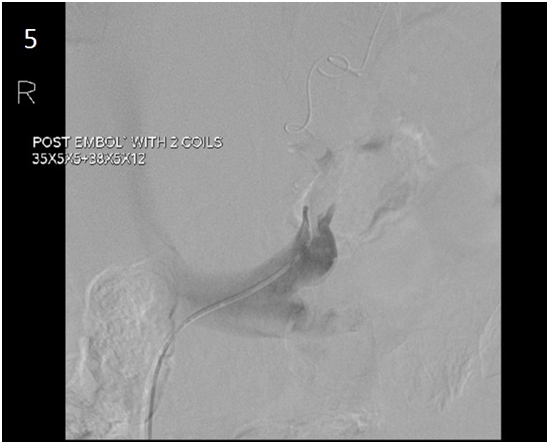

Figure 5 Venography. After transcatheter embolization of the shunt with coils.